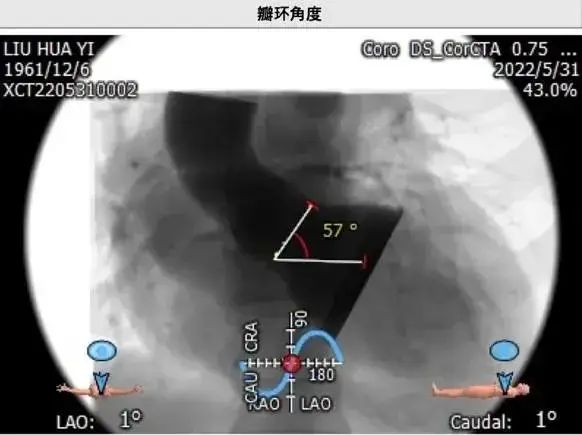

• 瓣上4mm/6mm预估可推开空间周长63.2mm/61.9mm。瓣环角度57度。

瓣环角度57度